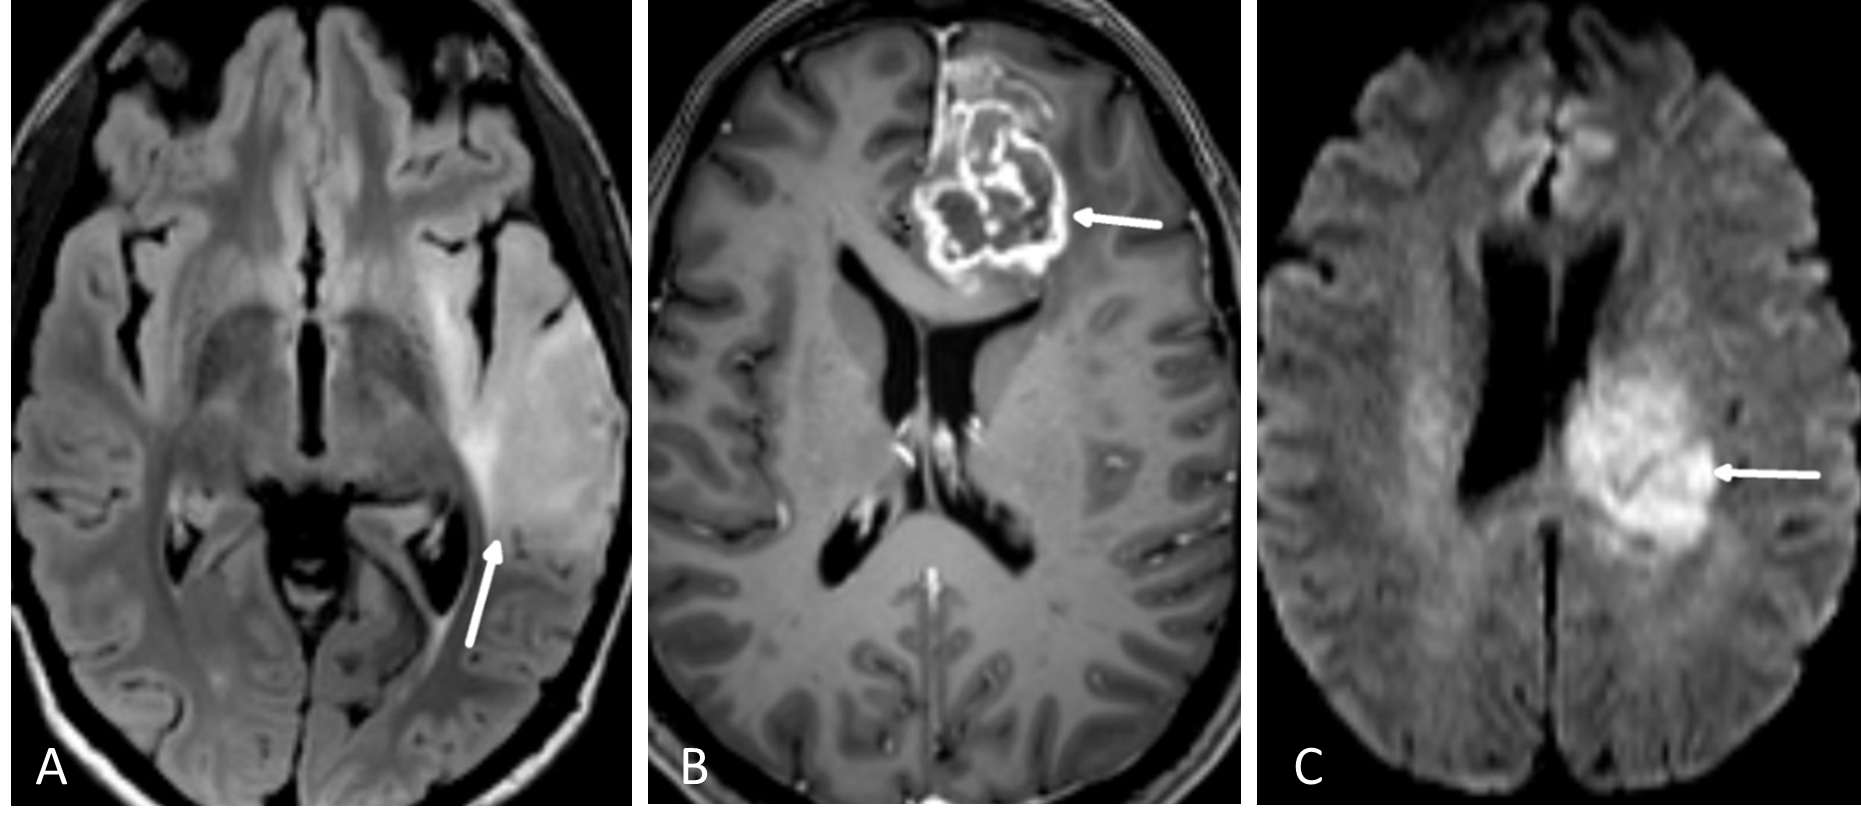

T2-vektede sekvenser

På T2-vektede sekvenser vil cerebrospinalvæsken være lys, mens hvit hjernesubstans vil være litt mørkere enn grå substans. Siden nesten all patologi i hjernen som tumor, infarkt og inflammasjon medfører økt mengde vann i vevet, vil patologi som en hovedregel lyse opp, altså ha høyt signal, på T2-bilder. Den mest brukte T2-sekvensen i hjernen heter turbo (eller fast) spin ekko (TSE-T2). En tumorprotokoll vil nesten alltid inkludere en T2-sekvens i transversalplan.

FLAIR

FLAIR er en MR-teknikk hvor man har eliminert det lyse signalet fra cerebrospinalvæsken i en T2-vektet bildesekvens (Figur 5.1). Man kan tro at når signalet i cerebrospinalvæsken undertrykkes blir også vann i en tumor svart. Det er imidlertid forskjell på MR-egenskapene til såkalt fritt vann (som i cerebrospinalvæske) og såkalt bundet vann som interagerer med blant annet makromolekyler i cellemembraner (som i en tumor). FLAIR-sekvensen er laget slik at det bare er det frie vannet som undertrykkes, mens bundet vann i patologiske lesjoner fortsatt lyser opp. En hjernetumorprotokoll vil alltid inneholde en FLAIR-sekvens, vanligvis som et 3D-volum som kan rekonstrueres i valgfrie bildeplan. Særlig på lavgradige, diffust infiltrerende svulster er FLAIR den mest sensitive bildesekvensen.

T1-vektede sekvenser

På T1-vektede MR-bilder av hjernen er cerebrospinalvæsken svart, fett i benmarg og underhud er lyst, mens hvit hjernesubstans er lysere enn grå substans. De mest brukte MR- kontrastmidler er gadolinium-chelater som gis intravenøst. Vev som tar opp kontrastmidlet får høyere signal (blir lyst) på kontrastforsterkede T1-bilder. MR-kontrastmidler krysser ikke en intakt blod-hjerne-barriere. Høygradig maligne hjernesvulster (CNS WHO grad 3-4), metastaser og meningeomer vil som regel lade opp kontrast, mens lavgradige nevroepiteliale svulster (CNS WHO grad 1-2) ofte ikke har kontrastopptak (Figur 5.1). Det er dog ingen absolutt sammenheng mellom kontrastopptak og graden av aggressivitet i svulsten. Alle tumorprotokoller inneholder T1-sekvenser før og etter intravenøs kontrast, enten som bildeopptak i transversal- og koronalplan, eller som et 3D-volumopptak som rekonstrueres i valgfrie bildeplan. Det sistnevnte er nå det vanligste. Det er et viktig poeng at ikke alt som lyser opp på T1-bilder er kontrastopptak, for eksempel har også blod og fett høyt T1-signal. For å unngå feiltolkning inneholder derfor tumorprotokollen også en T1-serie før kontrastinjeksjon.

Diffusjonssekvenser

Bildekontrasten på diffusjonsbilder avhenger av vannmolekylenes mobilitet i vevet. Mobiliteten til vannmolekylene er høy i rommet mellom cellene, men lav inne i cellene. Hjernesvulster med høy celletetthet som lymfomer og medulloblastomer, har lav diffusjon. Høygradige gliomer (CNS WHO grad 3 og 4) har høyere celletetthet og dermed lavere diffusjon enn gliomer med lavere malignitetsgrad (Figur 5.1). Diffusjonsvektede bilder er også nyttige for å skille mellom nekrose og abscesser.